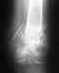

Заочно и без рентгеновсикх снимков вряд ли можно что-то определенное посоветовать. Может быть, надо лишь подобрать удобную амортизирущую обувь, может быть, без операции не обойтись.